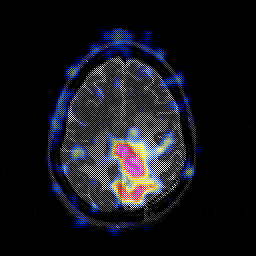

Glioblastoma multiforme overlay -- Slice #39

[Home][Help][Clinical][Tour 1][Tour 2][Tour 3] Slice 39